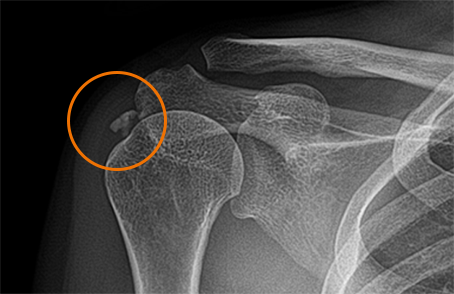

석회

회전근개 힘줄 안에서 발생

석회가 있었다는 것은 이미 수 년동안 회전근개쪽에도 문제가 있었다는것을 의미

석회의 상태

형성기

석회가 분필처럼 말라서 딱딱하게 굳어져있는 상태

대부분 증상이 없으며 우연히 발견됨흡수기

석회가 치약처럼 말랑말랑해져 있는 상태

극심한 통증을 유발하는 경우가 많다.